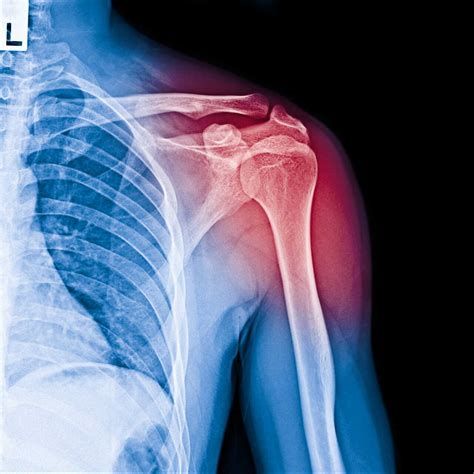

골절 부위별 수술비용이 큰 영향을 미치는 요소는 무엇인가요

골절 부위별 수술비용에 큰 영향을 미치는 주요 요소는 아래와 같습니다.

- 골절 부위의 해부학적 특성

- 부위가 클수록(예: 대퇴부, 척추 등) 수술 난이도와 위험도가 높고, 사용되는 재료도 더 복잡하거나 많아져 비용이 증가합니다.

- 예를 들어, 머리뼈/얼굴뼈 골절 진료는 발생 빈도가 높지만, 실제 진료비 비중은 넓적다리뼈(대퇴부) 골절이 가장 높으며, 이는 해당 부위 수술이 복잡하고 후유증·합병증 가능성이 커 고가 치료가 요구되기 때문입니다.

- 수술 방법과 사용 재료

- 단순 내고정술, 나사 고정 같은 표준 수술과 비용이 낮은 표준재료 사용 시 저렴합니다.

- 인공관절 치환술, 외고정술 등 고난이도 수술법 또는 특수·수입산 재료(비급여) 사용 시 비용이 크게 늘어납니다.

- 골절의 복잡성 및 중증도

- 단일 청결 골절의 경우 수술과 입원 기간이 짧아 비용이 적게 듭니다.

- 분쇄(여러 조각), 개방성 골절 등은 수술이 복잡해지고 재활 기간·입원 일수가 길어져 고가로 이어집니다.

- 입원 기간과 추가 치료

- 골절이 심하거나 환자 상태가 나쁘면 입원 및 재활치료 기간이 길어져 비용이 증가합니다. 대퇴골절의 경우 평균 22.3일, 최대 36일까지 입원이 길어져 진료비 부담이 크다는 점이 대표적입니다.

- 환자 상태(나이, 기저질환 등)

- 노인층은 골절 후 회복이 느리고 합병증 위험이 높아, 치료와 수술이 복잡해지고 비용이 높아지기 쉽습니다.

- 만성질환 등 환자 기저 건강상태가 좋지 않을수록 추가 관리와 치료비가 발생합니다.

- 의료기관 규모 및 지역

- 대학병원, 상급종합병원, 대도시 소재 병원 등은 첨단 장비·인력에 따른 기본 진료비가 상승할 수 있습니다.

- 재수술 및 합병증 발생

- 재수술이 필요한 경우, 표준 수술 대비 더 높은 수술비가 책정되거나 고가 재료 및 추가 진료가 발생할 수 있습니다.

요약하면, 골절 부위 자체의 난이도, 수술 방식 및 재료 사용, 입원·재활 기간, 환자 특성과 병원 종류 등이 골절 부위별 수술비용의 주요 결정 요인입니다. 특히 대퇴부·척추 등은 수술 및 입원 난이도가 높아 가장 고가 진료로 집계되고, 손가락·발가락 등 작은 부위는 간단할수록 저렴하게 산정됩니다